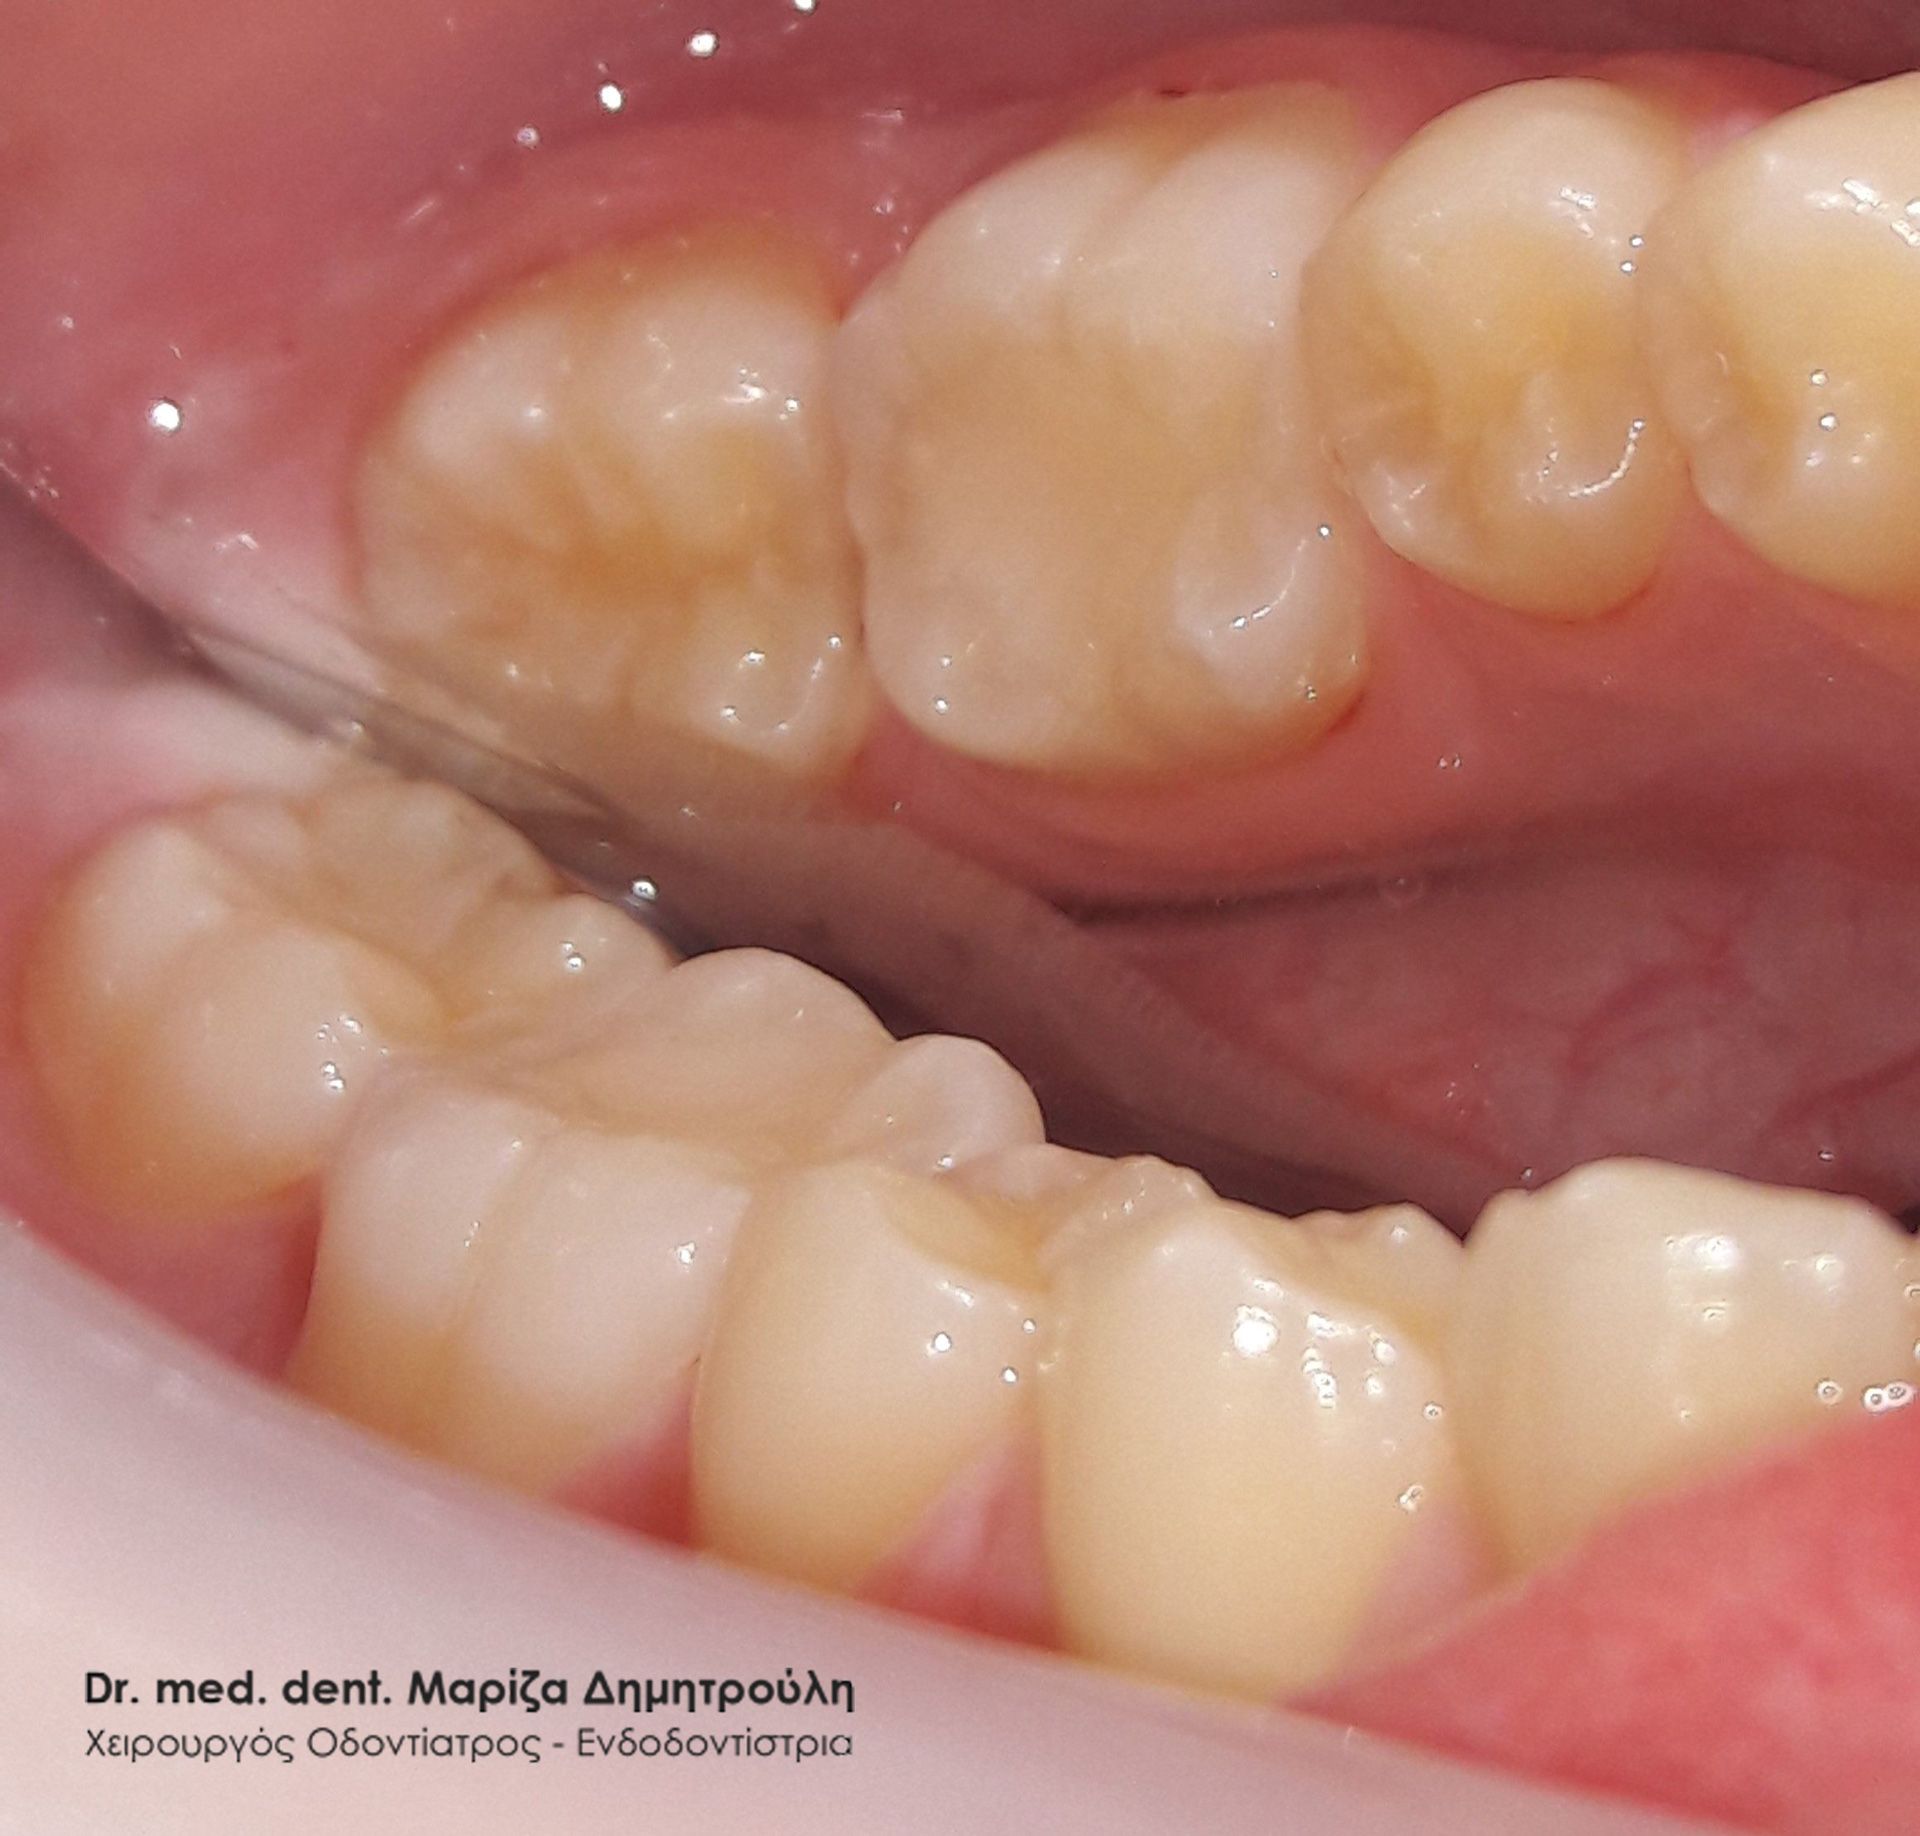

Στην έφηβη αυτή μικρή κυρία πραγματοποιήθηκε προληπτική κάλυψη της μασητικής επιφάνειας του μόνιμου άνω πρώτου γομφίου, για την προστασία του δοντιού από την τερηδόνα. Εφόσον η μασητική επιφάνεια ενός δοντιού καλύπτεται με υλικό sealant μειώνεται ο κίνδυνος προσβολής από τερηδονογόνα μικρόβια, καθώς συγκεντρώνονται λιγότερα μικρόβια και υπολείμματα τροφών στη μασητική επιφάνεια ενώ παράλληλα το παιδί μπορεί να βουρτσίζει πιο αποτελεσματικά και εύκολα. Ο χρόνος ζωής ενός sealant κυμαίνεται από 2 – 5 χρόνια.

ΠΡΙΝ

ΜΕΤΑ